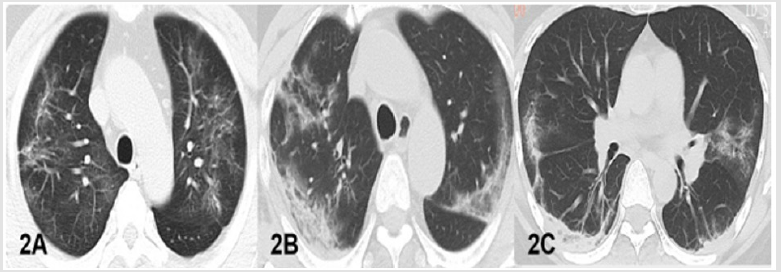

a. Case1 Man, 56Y, with fever, dry cough for 8 days, exposed to Wuhan, was admitted to the hospital and new coronavirus nucleic acid tested positive in other hospital. But twice new coronavirus nucleic acid tests were negative duration of hospital stay. The patient underwent plain chest CT scan (Figure 2). The patient remains in isolation.

Figure 2: CT findings of NCP. A. Case1 in cured group, chest CT displayed multiple fiber strip and ground glass shadow in both lungs. B. B-C. Case1 and 3 in isolation group and, the chest CT displayed multiple patchy, ground-glass densified shadows with partial consolidation, a little fiber under the pleura in both lungs.

c. Case 3 Woman 38Y, with fever, dry cough for 13 days and shortness of breath for 7 days, returned from Hubei province. The new coronavirus nucleic acid was positive in other hospital. But three times of new coronavirus nucleic acid tests were all negative. The patient underwent chest CT (Figure 2). The patient remains in isolation.

In the cured group, the lung lesions in all patients showed a significant decrease in absorption, however,2 patients (2/3) were still with obvious ground glass or fiber strips (Figure1), but no consolidation were observed. 2 patients in isolation treatment group, multiple GGO, fibrosis and consolidation were observed (Figure 2). Our results showed that chest CT findings GGO and fibrosis had overlap in cured group and isolation group (Figure 2). Two cases in isolation group, the main CT findings were highly similar to that of cured patients.